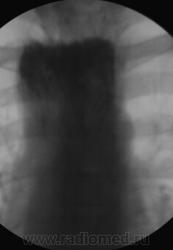

Неужели ахалазия?

Практически патогномоничная картина выраженной ахалазии кардии...

Именно так. Просто случай очень уж запущенный, редко такое увидишь - как в учебнике!

Посмотрите как выглядит грудная клетка при ахалазии 4-й степени